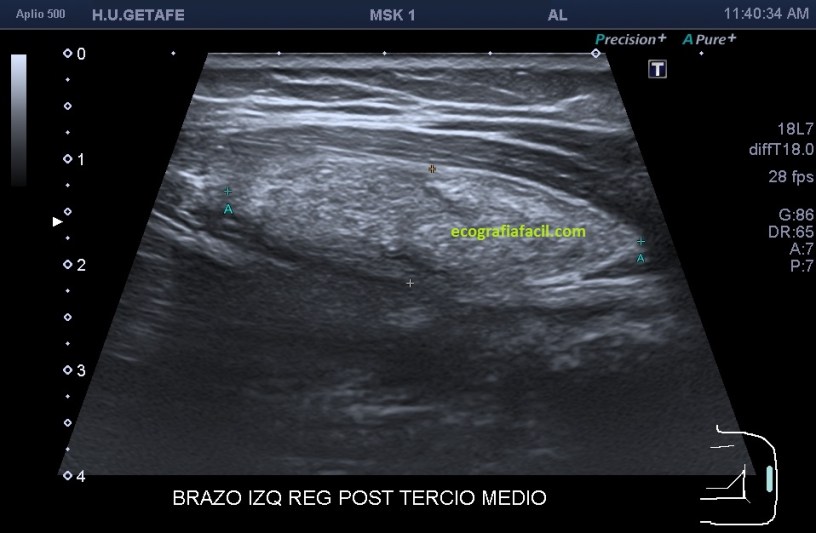

Si está por debajo, es decir, en el músculo como es en este Caso 3 que ves a continuación, la transmisión del sonido y la visualización del lipoma podrían serán peores, son los conocidos como lipomas intramusculares…mira el caso que te presento a continuación:

Como ves en este tercer caso del Post, es una mujer con un bulto en el brazo, en la localización que marcan las imágenes. El aspecto es hiperecogénico, respecto del músculo que lo envuelve que como muy bien sabes es hipoecogénico por definición. Los márgenes están marcados y definidos y el lipoma intramuscular está perfectamente localizable dentro del músculo. Su aspecto ecogénico es ligeramente heterogéneo. No tiene vascularización. Para ser un lipoma intramuscular se ve muy bien ya que está situado en una extremidad, como he mencionado anteriormente, en la cintura escapular o en paravertebrales que suelen ser habituales estos lipomas intramusculares, su visualización será un poco difícil, por la mala transmisión.

Observa la imagen 12 y 13, que son la misma, para que veas cómo se sitúa el lipoma dentro del músculo, y sus márgenes, luego para que veas la ecoanatomía de la imagen. El protocolo de estudio es el mismo siempre, localización, medición, vascularización.